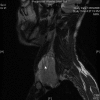

Case presentation: A 27 year male presented with a gradually enlarging, asymptomatic swelling on left supraclavicular region with normal overlying skin. A soft mass, about 7 x 7 cm with restricted mobility was found with normal cranial nerve function. Fine needle aspiration cytology showed a hemorrhagic aspirate. Doppler showed a mass displacing left carotid artery posteriorly while left internal jugular vein was not visualized. Magnetic resonance imaging showed a well defined mass isointense to hypointense on T1 weighted and hyperintense on T2 weighted and STIR images with fluid-fluid levels. On exploration, a vascular mass arising from left internal jugular vein was found with good tissue planes, which was excised after ligating the patent internal jugular vein above and below the lesion. Histopathologic examination confirmed the diagnosis of vascular malformation.